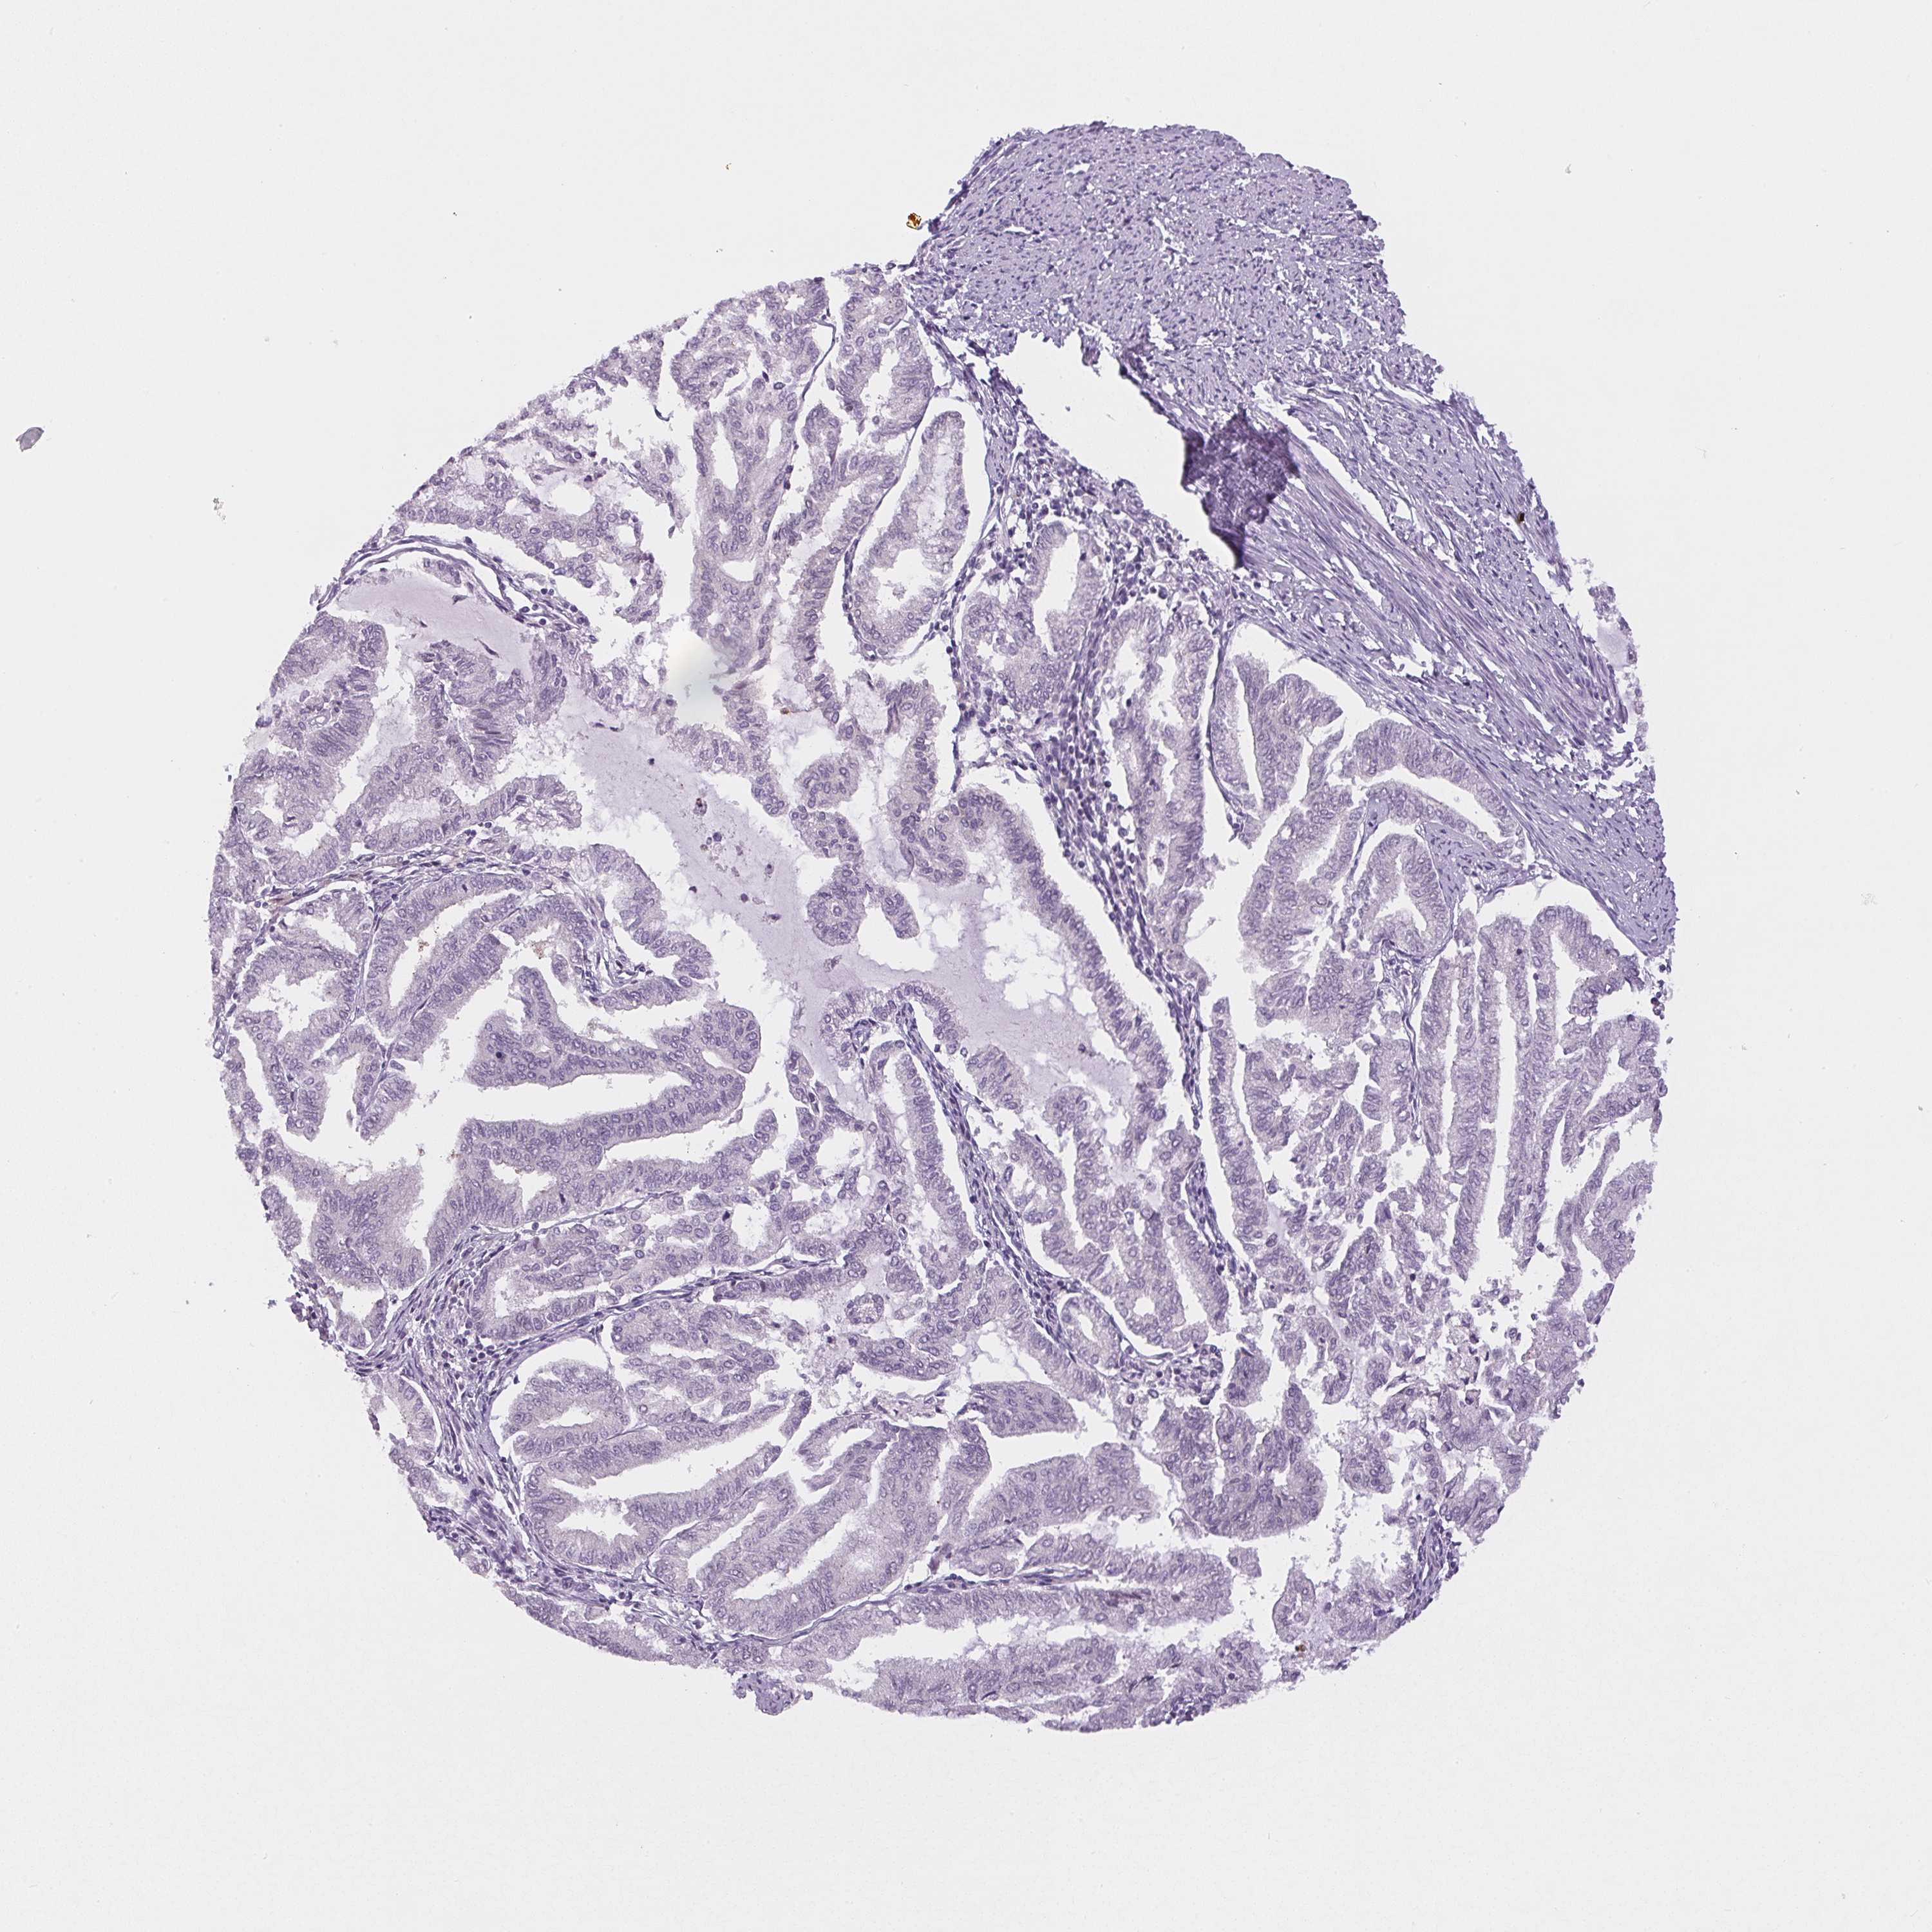

ENDOMETRIAL CANCER - Protein expressioni

A mouse-over function shows sample information and annotation data. Click on an image to view it in a full screen mode. Samples can be filtered based on level of antibody staining by selecting one or several of the following categories: high, medium, low and not detected. The assay and annotation is described here.

Note that samples used for immunohistochemistry by the Human Protein Atlas do not correspond to samples in the TCGA dataset.

Antibody stainingi

Antibody staining in the annotated cell types in the current human tissue is reported as not detected, low, medium, or high, based on conventional immunohistochemistry profiling in selected tissues. This score is based on the combination of the staining intensity and fraction of stained cells.

Each image is clickable and will lead to virtual microscopy that enables deeper exploration of all samples and also displays staining intensity scores, fraction scores and subcellular localization as well as patient and tissue information for each sample.

Antibody HPA052590

Antibody HPA053608

Staining

High

Medium

Low

Not detected

Intensity

Strong

Moderate

Weak

Negative

Quantity

>75%

75%-25%

<25%

None

Location

Nuclear

Cytoplasmic/membranous

Cytoplasmic/membranous,nuclear

Adenocarcinoma, NOS